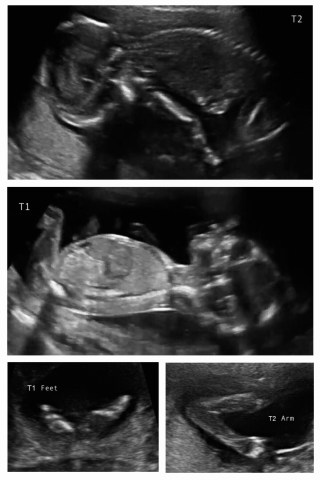

Lots of ‘good on you’s and lots of ‘you’re very brave’ (I’m not sure if that’s directed at the on my own, or the twin thing!) I’m not sure if I am brave, or stupid, I guess I’ll find out in September!